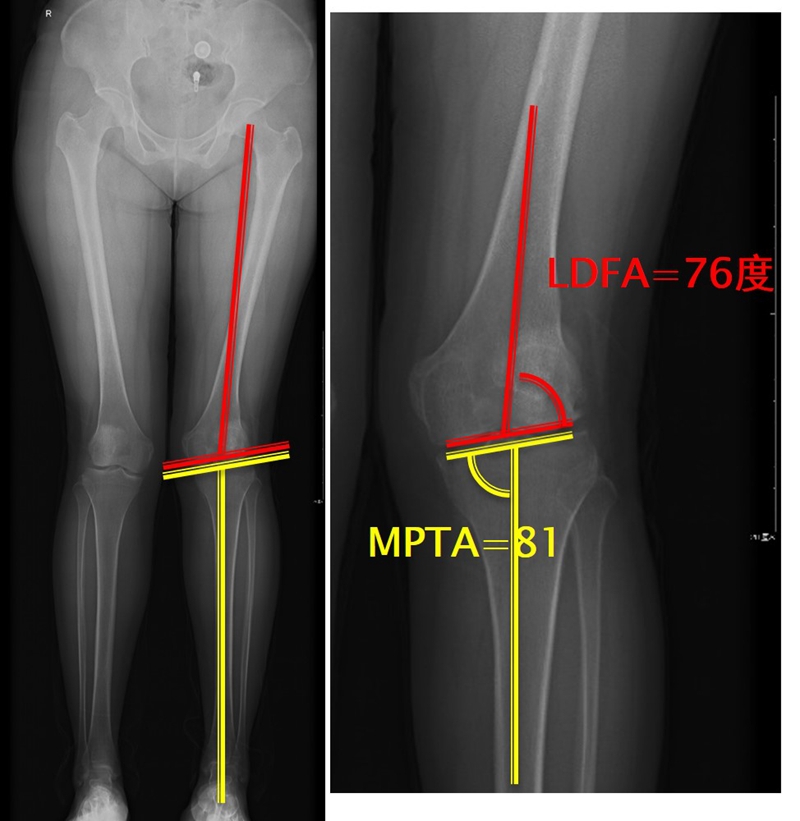

步骤二:判断畸形部位

量股骨远端外侧角和胫骨近端内侧角,判断畸形在股骨、胫骨还是关节内。此患者股骨侧有畸形,LDFA=76°,MPTA=81°,无关节内畸形。

步骤四:确定合页位置和截骨线方向

此患者计划股骨内侧闭合楔,胫骨内侧开放楔。

步骤五:Miniaci法测量角度

以股骨侧合页为旋转中心,以股骨头中心到合页的距离为半径,进行旋转,直到该线段与目标力线相重合,此时重合角度即为股骨需要闭合的角度,同时胫骨侧也能计算出开放的角度。此患者需要股骨闭合14°,胫骨开放8°。